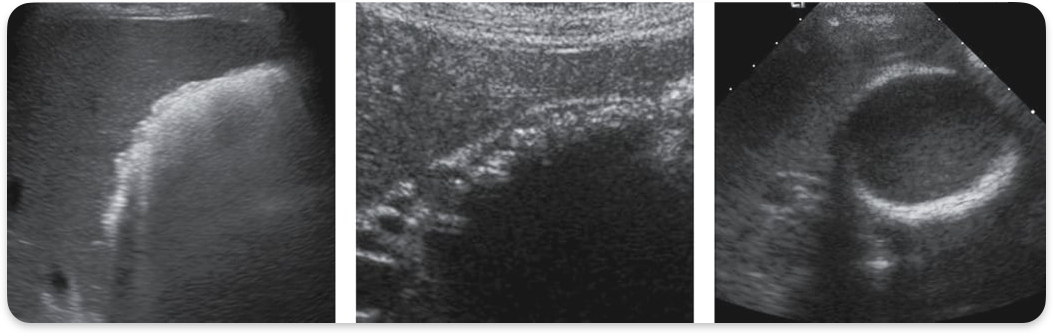

Polyps

Projection of tissue from GB wall into lumen

Most common type of gallbladder polyp

Cholesterol polyp

Polyps on anterior wall

Adenomyomatosis

Thickened wall, diverticuli (rokitansky Aschoff sinuses)

Rokitansky Aschoff sinuses

Pockets in gallbladder wall containing cholesterol crystals, causing comet-tail artifact. (Adenomyomatosis)